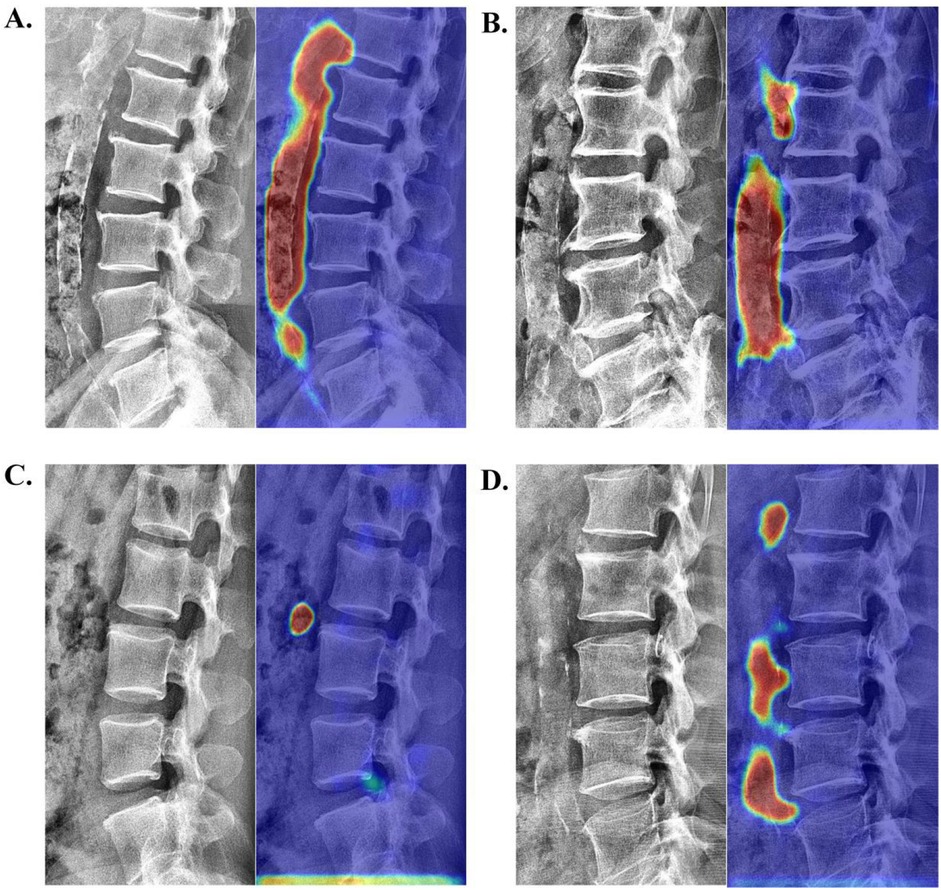

Visual interpretation analysis

To qualitatively verify the model's accuracy in localizing calcifications, we employed Grad-CAM (26) for visual explanatory insights. The results demonstrated strong agreement with radiologist assessments (78.35% correct focus; Supplementary Table S2) in the internal validation set. Figure 5 displays four randomly selected representative cases with distinct cardiovascular risk profiles involving: (A) chronic kidney disease, (B) hypertension, (C) hyperlipidemia, and (D) coronary artery disease. As exemplified in Figure 5A, the model's attention heatmap comprehensively covered nearly all AAC calcification areas, yielding a predicted AAC score of 22 points, which closely matched the manual score of 23 points.

Figure 5

Visualization of neural network activation maps from the developed automated AAC scoring system for four randomly selected representative cases with distinct cardiovascular risk profiles involving: (A) chronic kidney disease (manual AAC score: 23; model-predicted score: 22), (B) hypertension (manual AAC score: 19; model-predicted score: 17), (C) hyperlipidemia (manual AAC score: 1; model-predicted score: 1), and (D) coronary artery disease (manual AAC score: 10; model-predicted score: 11).